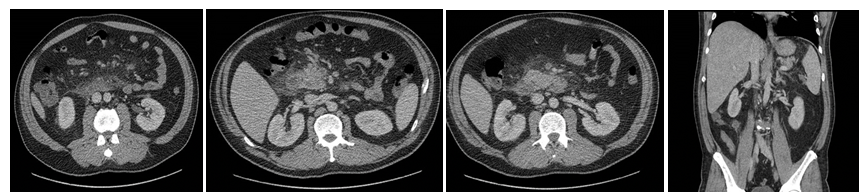

A 75-year-old male patient presents with a clinical picture of 4days of fever, LIF abdominal pain and jaundice. Clinical history was positive for a laparoscopic gallbladder removal. The patient had a BP of 85/60mmHg, HR of 91bpm, RR of 22rpm, temperature of 38.2, jaundice without peritoneal irritation. Significant lab findings included thrombocytopenia of 82.000, Creatinine of 2.62, Total bilirubin of 4.3 Direct bilirubin of 3.5 indirect bilirubin of 0.8, Alkaline phosphatase of 161, normal liver enzymes, and ABGs showing metabolic acidosis. The initial proposed diagnosis was an intra-abdominal septic shock. ICU managed included Noradrenalin, IV fluids, broad-spectrum antibiotics with Meropenem and Linezolid.  Initial Contrast abdominal CT showed a sigmoidal Hinchey 1A diverticulitis (Figure 5). Abdominal ultrasound showing a normal bile duct (Figure 6). Follow-up abdominal CT showing sigmoidal Hinchey 1B diverticulitis (microperforation), left intrahepatic portal vein thrombosis (Figure 7). Bile system MRI showing a common bile duct of 7.2mm (Figure 8). Despite treatment the patient had persistent bilirubin elevation of up to 11 mg/dl and a blood culture positive for a resistant E.coli. The patient was taken to a diagnostic laparoscopy finding a sigmoid diverticulitis with a plastron of pericolic fat tissue. A laparotomy incision was performed finding significant venous thrombosis of the left colic vein and sigmoid vein requiring a left colectomy with a Hartmann colostomy. Pathology report confirmed venous thrombosis. The patient had full recovery with antibiotics and was discharged.

Figure 5 Hinchey 1A sigmoid diverticulitis.

Figure 7 Hinchey 1B sigmoid diverticulitis (microperforation) and left intrahepatic portal vein thrombosis.